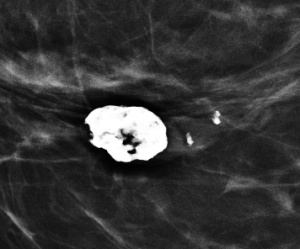

Magnification views were performed for the right breast calcifications seen on a screening mammogram:

E. Popcorn-like calcification

Explanation: These are the large, coalescent, coarse or “popcorn-like” calcifications that are typical of an involuting fibroadenoma.

There are actually probably two or three adjacent fibroadenomas in this location. The dominant large calcification represents the end stage of an entirely calcified involuting fibroadenoma. The smaller adjacent popcorn-like calcifications represent an earlier stage of involution in a different fibroadenoma.